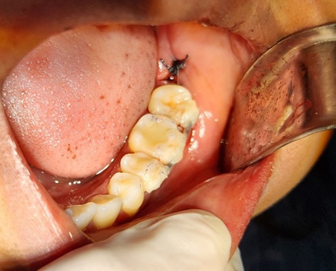

bajo anestesia local. Se efectuó una incisión para reflejar un colgajo envolvente y se extrajo el órgano dentario afectado. Posteriormente, se reposicionó un tercer molar en un nuevo alveolo previamente modificado para corregir una supra oclusión. El colgajo fue reubicado y se realizó la ferulización del tercer molar en la posición del segundo molar (Figura 1).

Fig 1. Tercer molar en posición de segundo molar ferulizado.